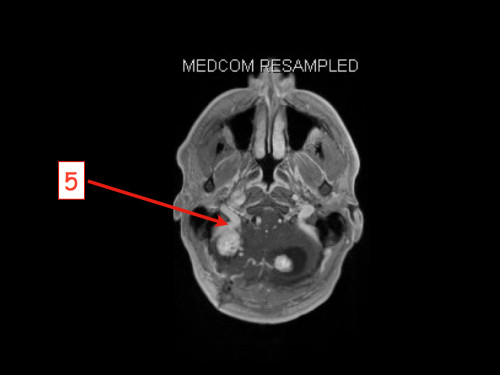

3. Schwindel und Kopfschmerzen, 3 Jahre nach Phäochromozytom-Resektion

Schwindel und Kopfschmerzen, 3 Jahre nach Phäochromozytom-Resektion

19-jähriger Mann. Er klagt seit mehreren Wochen über Schwindel und Kopfschmerzen. Im Alter von 16 Jahren sind er und sein Zwillingsbruder an einem Phäochromozytom operiert worden.